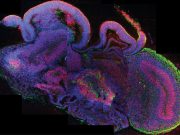

Laboratuvarda beyin üretmek: Embriyonik fikir

Bir grup kök hücre biyoloğu beyne benzeyen bir “organoid” geliştirdiler.

Rejeneratif (onarıcı) tıp kök hücrelerden doku ve organ üretiminden dolayı hızla gelişen bir alan. Fakat...